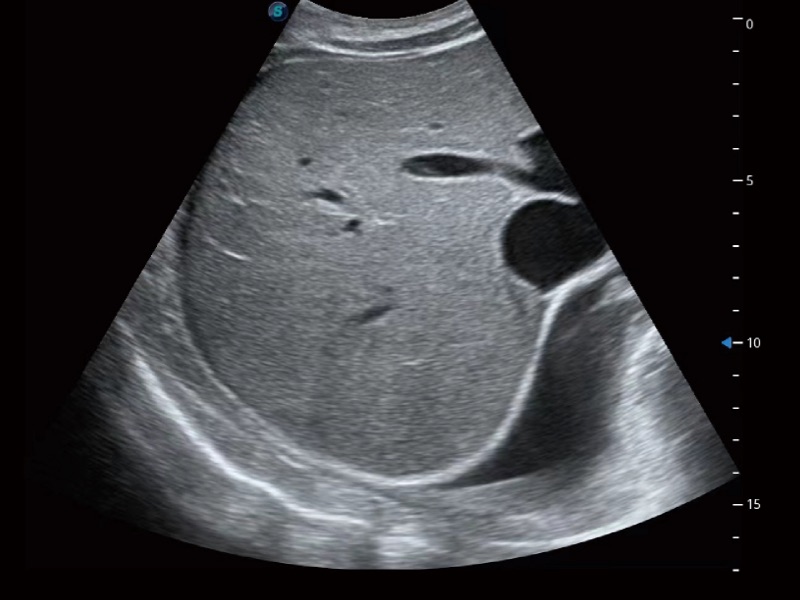

临床图